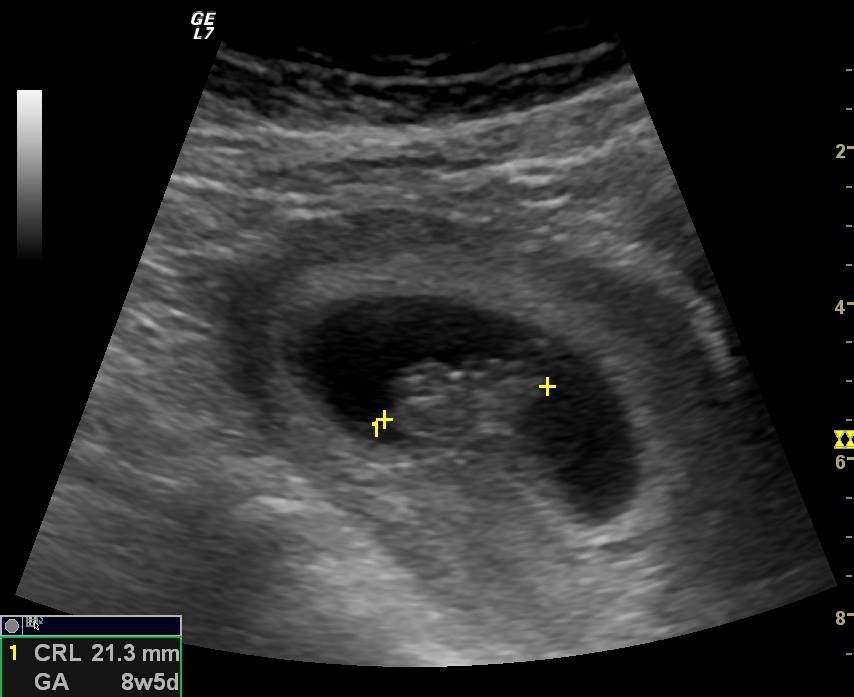

Just came home from today's ultrasound, I am 8/5 but baby is measuring bigger at 9/4! HR of 167! It was perfect! DH and I have decided not to find out the sex of the baby but are going to try out all the old wives tales and see how it weighs out for us and what we actually end up with! Of coarse we know none of them are guaranteed but the guessing is fun! I have attached an ultrasound photo, it was done abdominally so the image is mirrored. It looks pretty central to me so I'm hoping to get your opinion on it! Ramzi says right side=Boy and left=girl. Our next ultrasound won't be until around 20 weeks. Again, it's all in fun. Any opionions welcome!